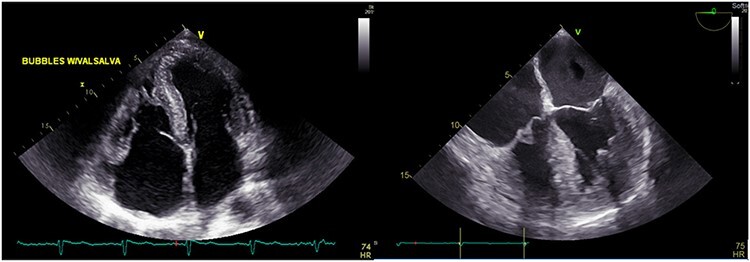

A 75-year-old male presented with progressive DOE for the past 1 ½ years. The patient used to be an avid runner. His PMH was notable for scleroderma, OSA and paroxysmal AFib. Investigations reported negative TnI, elevated NT-proBNP at 2880 pg/ml and LQRSV. TTE was suggestive of infiltrative cardiomyopathy (Fig. 3). Cardiovascular magnetic resonance imaging (CMR) was suggestive of infiltrative cardiomyopathy (Fig. 4). The positron emission tomography scan was nonrevealing. BMBA showed increased plasma cells. Myeloma fluorescence in situ hybridization was positive for translocation 11;14 and monosomy 13 and negative for TP53 deletion. Abdominal fat pad biopsy was positive for amyloidosis (Fig. 5).

Figure 3 .

TTE showing speckled myocardium suggesting infiltrative cardiomyopathy, moderate concentric left ventricular hypertrophy (LVH) and bi-atrial enlargement.

Figure 4 .

CMR showing concentric left ventricular hypertrophy.